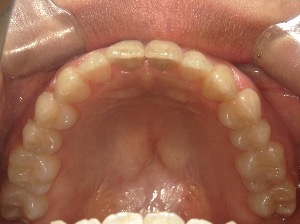

before

after

患者さんの年齢 20代 女性 症状 ガタガタを治したい 治療内容 マウスピース矯正治療 費用 90万(税抜) 治療期間・回数 治療期間2年、通院回数10回 メリット 笑顔が綺麗 デメリット・リスク 期間がかかることがある - マウスピース矯正